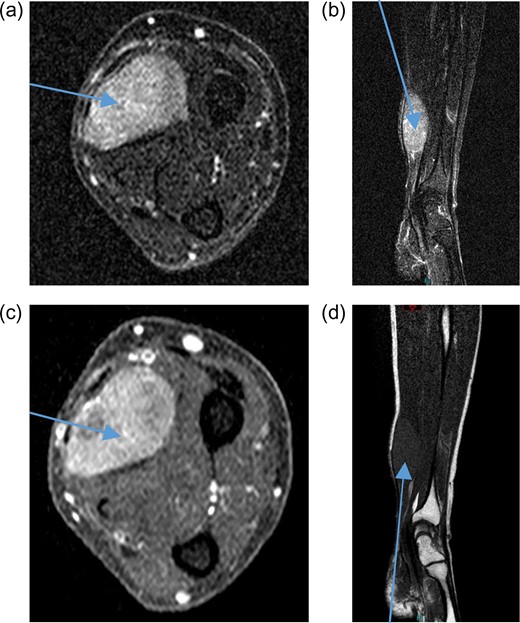

A 71-year-old male was referred to sarcoma clinic on 11/9/2017 with a painless swelling in his right forearm. He had a previous history of primary retro-peritoneal leiomyosarcoma surgery in 2011 with subsequent liver and lung metastases for which he underwent surgical resection in January 2017. His other past medical history included benign prostatic hypertrophy (controlled with medication), otherwise he was fully mobile, fit and well. This right-hand dominant male described a gradual 3-month history of increasing painless swelling to the volar aspect of the right forearm with full function of the arm and no neurological deficit. On clinical examination, there was a soft 5 × 4 cm swelling, 5 cm proximal to wrist crease in the volar compartment of the right forearm. The swelling was fixed, non-tender with no distal neurovascular deficit and or regional lymphadenopathy. Magnetic resonance imaging (MRI) of the right forearm demonstrated a 45 × 33 × 19 mm mass in the volar aspect in close relation to the median nerve (Fig. 1). Ultrasound-guided needle core biopsy was consistent with LMS and the histology was similar to the previous LMS suggesting the possibility of metastatic LMS. Staging studies did not show any other metastatic deposits. Following multidisciplinary team discussion, he underwent planned marginal excision of the metastatic sarcoma with preservation of the median nerve. Histology confirmed LMS composed of spindle cells with eosinophilic cytoplasm with mild pleomorphism confined within the perimysium with no necrosis or vascular invasion (trojani grade 1). The patient recovered well post operatively with no neurological deficit only complicated with a mild episode of cellulitis to the wound site which fully resolved with a short course of oral antibiotics. One year after surgery, the patient has full function and use of his right hand and there is no evidence of LMS recurrence or further metastatic spread both clinically and radiologically on recent CT scan of his chest, abdomen and pelvis and MRI scan of the forearm (Fig. 2).

Post-treatment contrast MRI of the forearm showing curative resection and no evidence of recurrence in the flexor compartment (a) sagittal T1, (b) sagittal T2 and (c) coronal T1.